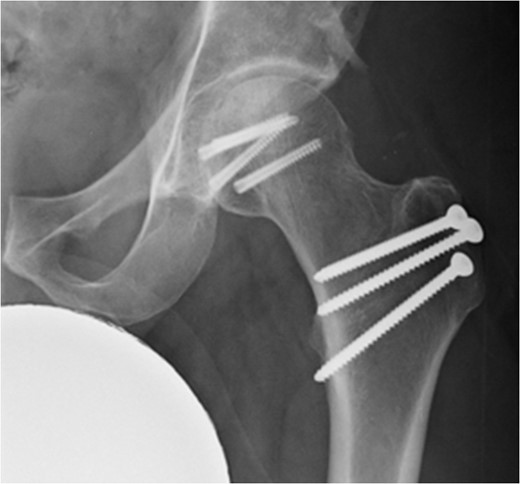

In addition to the bony injury, labral detachment and tearing were noted (later repaired with suture anchors). The femoral head was comminuted and had areas of missing articular cartilage especially posteriorly and superiorly with a 1 × 1 cm2 area of full thickness cartilage loss (Fig. 4). The weight-bearing zone was relatively unaffected. The ligamentum teres had to be released to allow fracture reduction and fixation with four headless compression screws (Fig. 5). A good fixation was achieved. Microfracture was performed on the articular cartilage defect. The femoral head, fracture fragment and microfracture site were bleeding and appeared viable.

Intraoperative view of the femoral head with temporary fixation with wires.

Intraoperative view of the femoral head after fixation with headless compression screws.